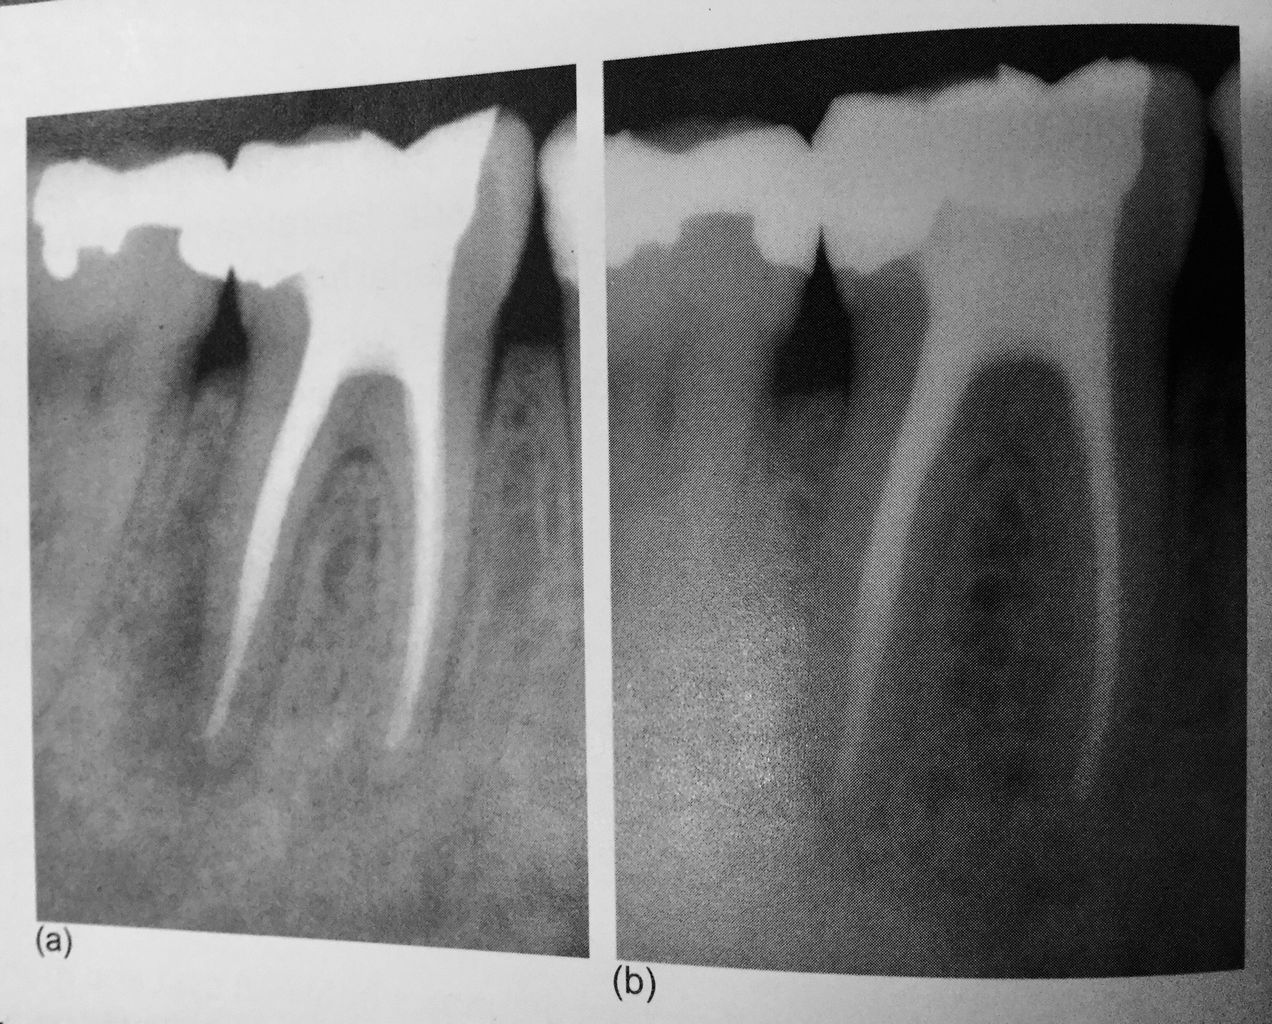

レントゲンで根の先が黒くなり、

膿んで骨がとけて、

ここに穴が開いてますね!

細菌が根の先にまで 進入してくると、

骨の細胞は細菌と戦えないんです。

一旦、骨がとけて肉芽って呼ぶ炎症性のお肉に変わります。

こんなに大きな穴でも、治ります。

少し根っ子を削るので、短くはなりますが。